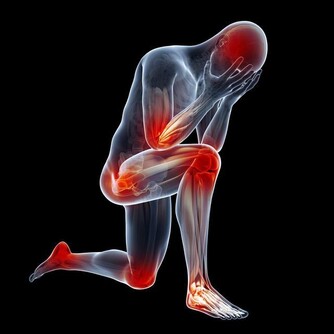

類似姚女士這樣,因為肩背疼查出其它疾病的患者不算少,

他提醒,天氣轉冷,肩背疼痛的患者也多了起來,

然而肩背痛不一定就是肩周炎或是頸椎病,它可能提示其它疾病:

1.如果感覺到了肩周炎的典型症狀:肩膀疼痛、關節活動受限,

但同時還有低熱、盜汗、乏力、臉色蒼白、消瘦等症狀,要提防肩關節結核。

2.肩部腫瘤也會引起肩痛、肩臂活動功能障礙,

如果覺得肩痛逐漸加重、疼痛部位擴大,可別再「惦記」肩周炎,一定要做進一步檢查。

3.多數膽囊炎的首發症狀是背疼,或是右肩、右肩胛下隱痛。

要還有噁心、腹脹、反酸、胃部灼燒感等消化不良症狀,別忘了去醫院做個彩超檢查一下膽囊。

4.患有高血壓的中老年人,突然覺得背疼,或是前胸、腹部疼痛難忍,

像是身體被刀割或是撕裂了似的,有可能是主動脈夾層,一定要儘快就醫。

如果搶救不及時,約四成患者可能會在24小時內死亡。

5.心絞痛、心肌梗死,也會放射至後背、左肩等部位,冠心病患者要是突然覺得肩背疼要小心。